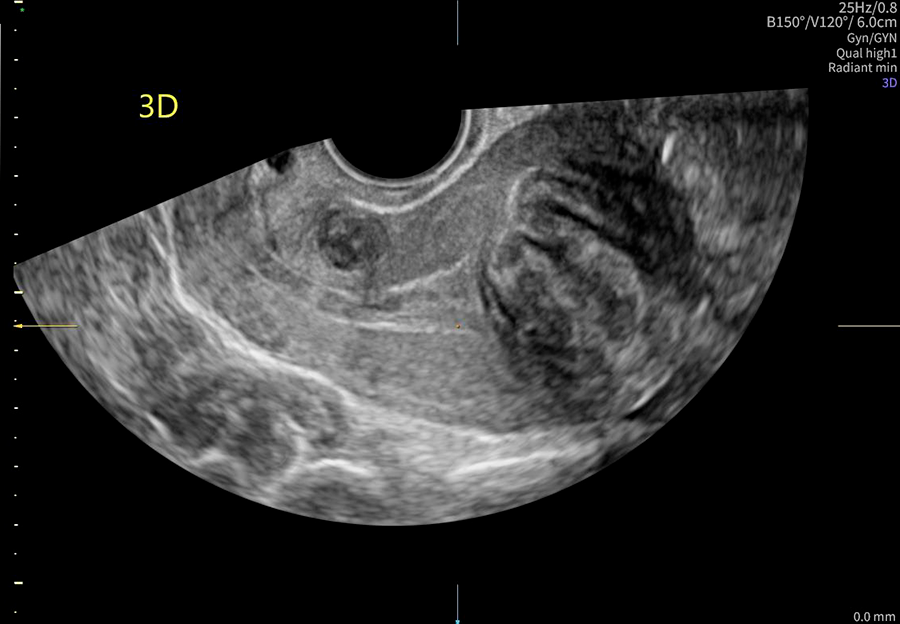

La ecografía ginecológica es un estudio por imágenes no invasivo que permite evaluar de forma precisa el útero, los ovarios y el sistema reproductor femenino. Es una herramienta fundamental para la detección temprana de alteraciones ginecológicas, el seguimiento de tratamientos y los controles preventivos.

En OBGYN Perú, realizamos ecografías ginecológicas con equipos de alta resolución, garantizando resultados confiables y una atención médica especializada.